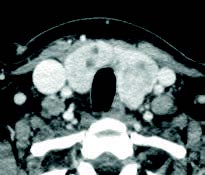

Mujer de 46 años que consulta por disfonía desde hace 2 meses, no fumadora, con antecedentes de hipertensión arterial y colesterol alto. En la exploración con fibroscopia naso-laríngea se aprecia parálisis de cuerda vocal izquierda. Como protocolo de las parálisis recurrenciales se pide TAC cérvico-torácico, para valorar el trayecto del nervio recurrente laríngeo, donde no se observan lesiones en mediastino o pulmón. Se aprecia gran crecimiento de la glándula tiroidea con lesiones quísticas y nodulares más intensas en lóbulo tiroideo izquierdo: bocio multinodular.